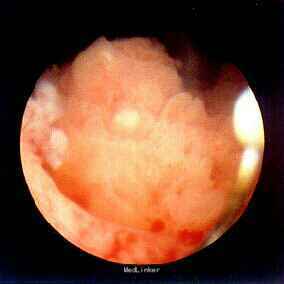

诊断:膀胱癌。 治疗:膀胱肿瘤电切术,术后使用吡柔比星膀胱灌注。

膀胱癌的发生是复杂,多因素,多步骤的病理变化过程。对分期相同的膀胱癌,女性的预后比男性差。男性膀胱癌高于女性,性激素可能是导致这一结果的重要原因。经尿道膀胱肿瘤切除术既是膀胱癌重要诊断方法,同时也是主要的治疗手段,经尿道膀胱肿瘤切除目的是切除肉眼可见肿瘤,二是进行病理分级和分期。turbt术应将肿瘤完全切除直至露出正常膀胱肌层。